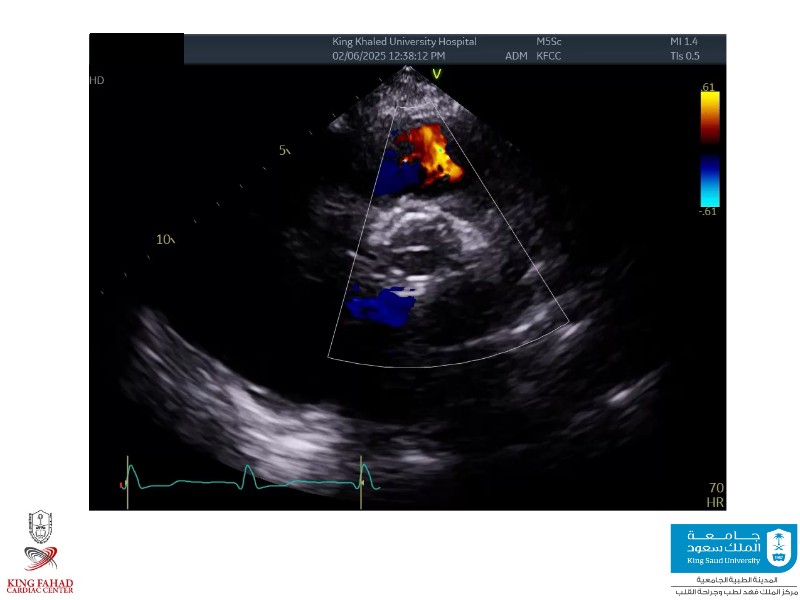

This session helps you anticipate and address complex scenarios such as mitral valve-in-valve, TAV-in-SAV, and valve-in-valve-in-valve procedures. Learn from expert case discussions that explore procedural strategies, technical challenges, and best practices to optimize outcomes in redo structural heart interventions.

- To anticipate and manage second valve scenarios with SAPIEN 3 Ultra RESILIA, including mitral valve-in-valve, TAV-in-SAV, and TAV-in-TAV